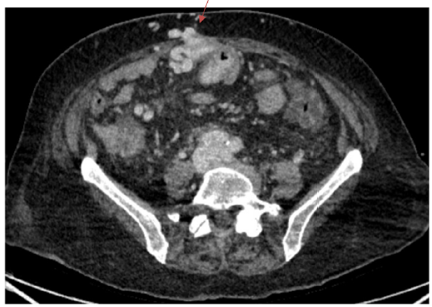

Femoral Arteriovenous Fistula Following Removal of Femoral Vein Catheter: A Case Report

Zhiming Zhang, Yuan Qin and Huidan Ouyang. 6(9): 01-03.